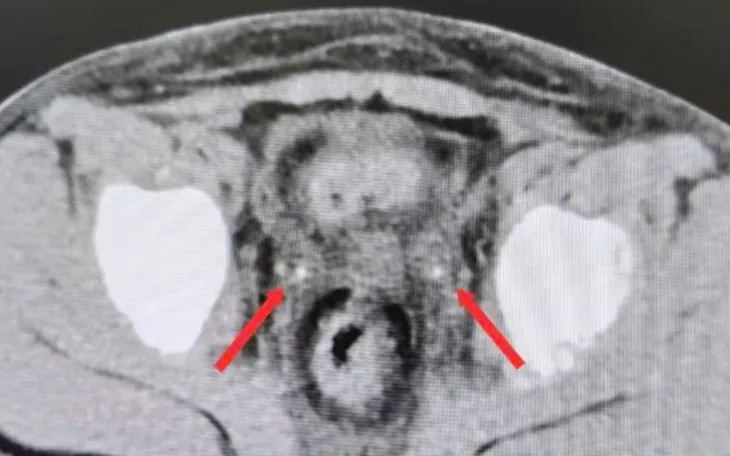

Chuyển đến Bệnh viện Nhi đồng 2 trong tình trạng không có nước tiểu, siêu âm không thấy nước tiểu trong bàng quang. Kết quả CT bụng không cản quang ghi nhận thận ứ nước hai bên, niệu quản giãn và sỏi kẹt đoạn cuối hai bên (phải 3x7mm, trái 3x20mm). Bệnh nhi được mổ cấp cứu trong đêm, nội soi bàng quang đặt ống thông JJ ngược dòng hai bên.